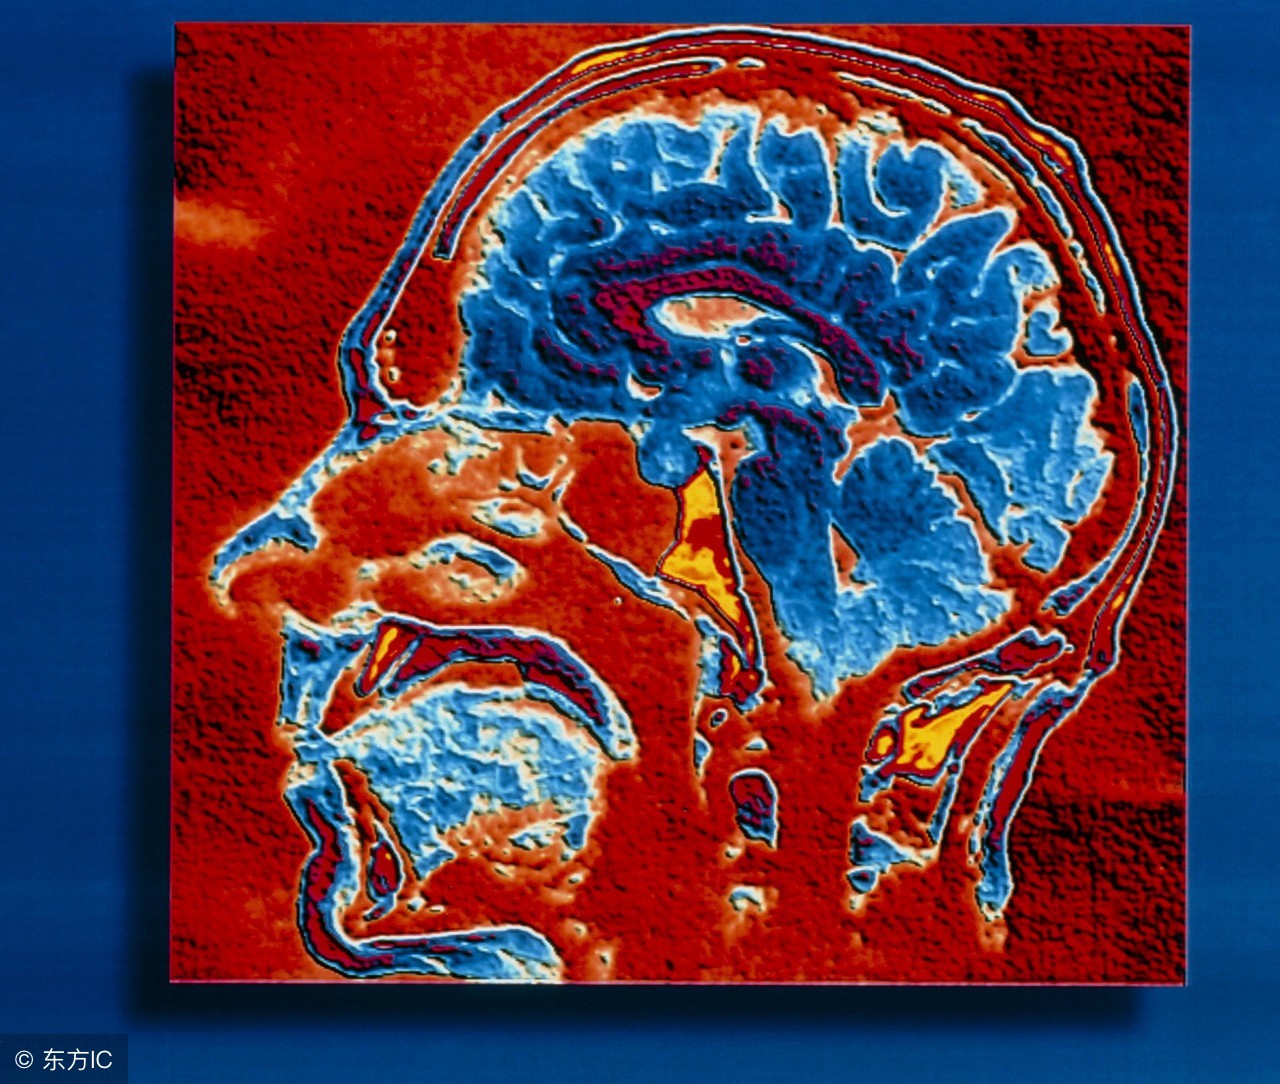

儿童脑瘤易被误诊为感冒,该病的误诊率高达50%。假如孩子头痛、呕吐、视力减退、走路不稳,就很可能是脑部患有肿瘤。而有些医生往往不重视,把它当平常的感冒。有类似症状的孩子要及时到医院做头部CT和MR检查,以免贻误病情。那么,儿童患脑瘤的症状是什么?